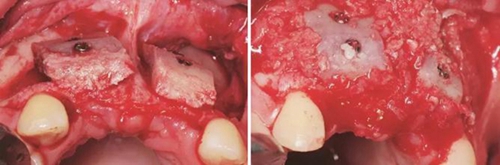

(2)2014年7月:行髂骨取骨,水平向Onlay植骨全麻下患者取平臥位,將取骨側(cè)的髂嵴墊高。標(biāo)記髂前上嵴,在髂嵴下方2cm處做切口,將局部的皮膚緊繃,使其位于髂嵴上方,切口方向同髂嵴,切開髂嵴中線外緣腱膜,剝離骨面附著肌肉至暴露足

夠骨面,使用骨鑿等取骨器械制取骨塊,填塞明膠海綿,分層縫合。口內(nèi)切開植骨區(qū)粘膜,翻瓣,充分暴露待植骨區(qū),用裂鉆在受骨區(qū)骨面預(yù)備若干滋養(yǎng)孔,修整骨塊,以器械夾持骨塊置于手術(shù)受植骨區(qū)并緊貼骨床,使用鈦釘牢固地固定骨塊,植骨塊間的間隙用自體骨屑及少量骨粉(Geistlich Bio-Oss,瑞士)混合后充填,充分減張后嚴(yán)密縫合創(chuàng)口。告醫(yī)囑,囑患者術(shù)后幾天盡量臥床休息,十天后拆線。拍攝CBCT示:牙槽嵴寬度擴(kuò)增明顯:12位點(diǎn)擴(kuò)增至7.4mm-12.4mm,22位點(diǎn)擴(kuò)增至7.4mm-12.2mm。

圖5 制取的髂嵴部骨塊 圖6 植骨術(shù)前牙槽嵴頂切開翻瓣

圖7 受植區(qū)固定髂骨骨塊 圖8 自體骨屑與人工骨粉混合后充填植骨間隙

圖9 嚴(yán)密縫合創(chuàng)口 圖10 植骨后拆線